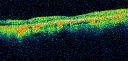

OCT SCAN: The OCT scan shows retinal atrophy.